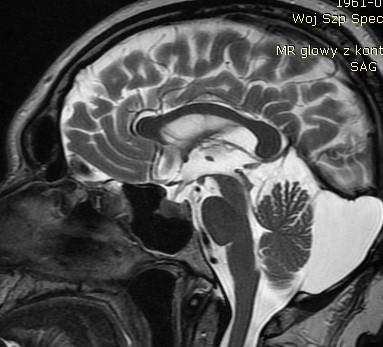

Zdjęcie przedstawia przekrój strzałkowy w sekwencji T2 rezonansu magnetycznego głowy. Struktury wskazane strzałkami odpowiadają lokalizacji: